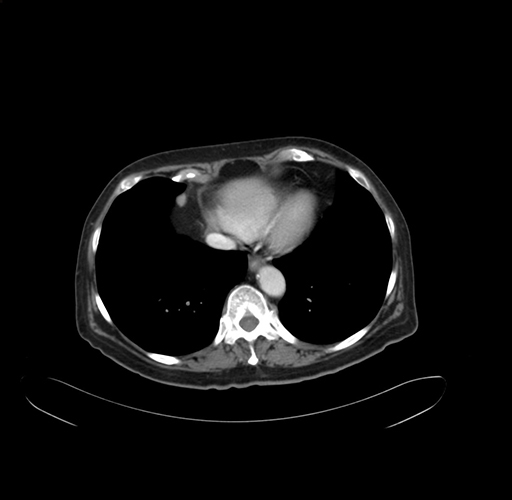

Pre-Chemo: Axial Venous